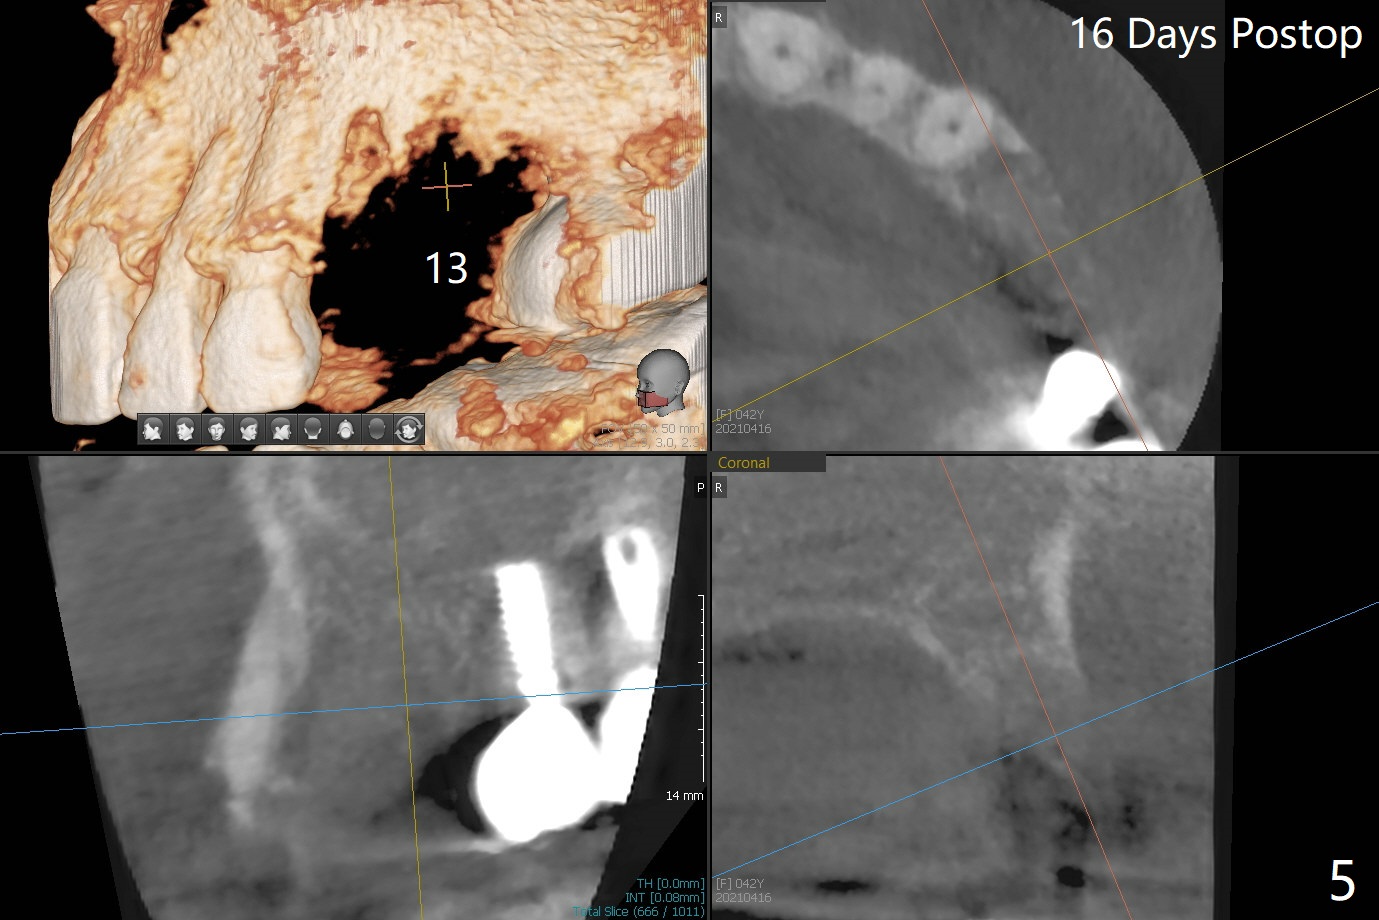

42岁女,12号牙断裂(图一),在拔除中不幸损伤13号牙,一起拔除,用GEM21S与异体骨和人工骨进行位点保存,术后骨粉一直脱落,病人觉得伤口有臭味。术后16天根尖片显示骨粉仍在牙槽窝(图二),伤口尚未愈合(图三),骨粉密度不高(图四,五)。讨论后,决定去除余留骨粉,重新刮拔牙槽窝,反复冲洗,最好放置粘性骨粉(图六),覆盖PRF和不可吸收膜,使用PTFE缝线,树脂敷料。术后三周膜和骨粉仍在原位(图七,八)。为了恢复龈乳头,术后四,五个月,利用导板去除两个牙位牙槽嵴骨质(图九),把植体植入牙槽嵴深部,之间便形成突起的牙槽嵴(图十:C)以及龈乳头。植牙整合后,利用临时牙冠,反复调整,挤压形成比较正常龈乳头。